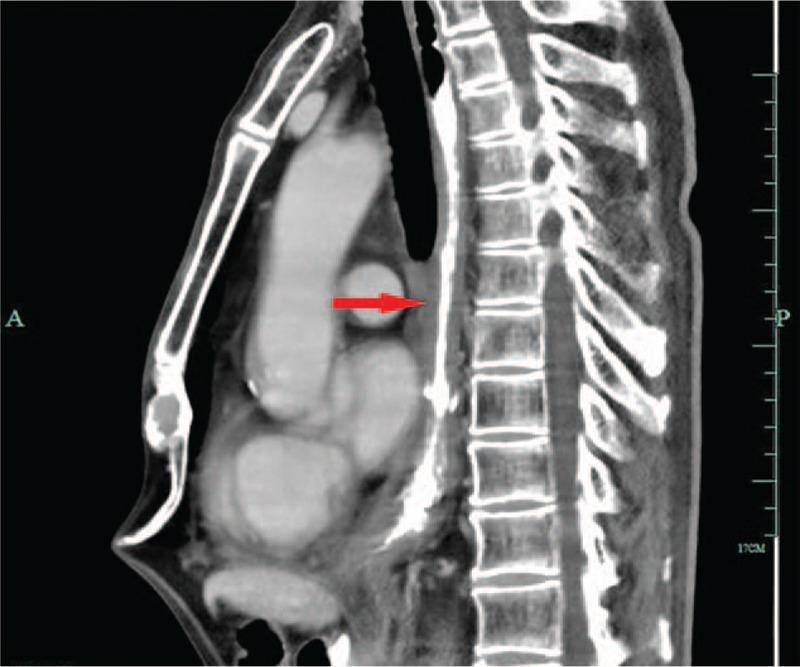

In this case report, we describe a case of a 59-year-old man who presented with difficulty in swallowing. Iohexol swallowing revealed a malignant-appearing structure in the inferior-thoracic region.

Biopsy of the lesion under endoscopy demonstrated a mucoepidermoid carcinoma of the esophagus.

在本病例报告中,我们描述了一名59岁男性患者,他出现吞咽困难。碘海醇吞咽检查显示胸段下部有一个疑似恶性的结构。

内镜下病变活检显示为食管黏液表皮样癌。